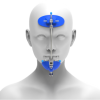

Корректор класса II Вильямса (исполнение 3) - Набор 320-0100

Описание товара